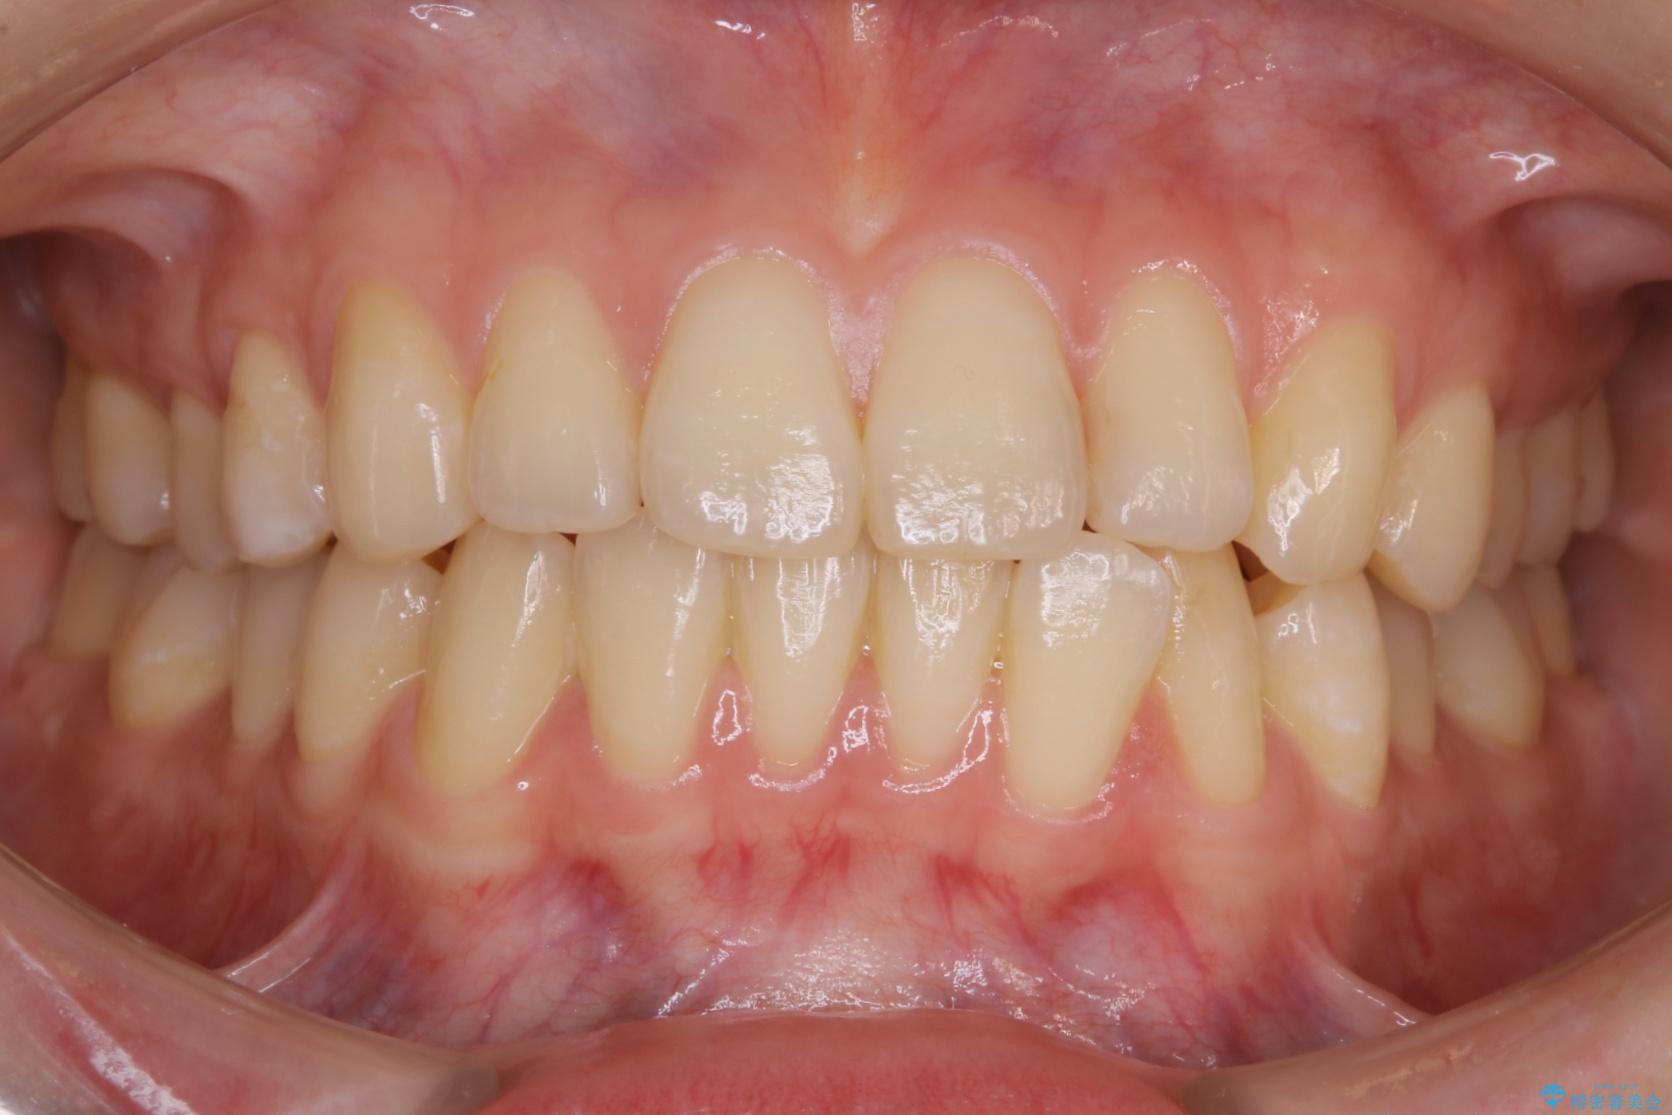

20代 女性 インビザラインで短期間矯正

- 20代女性

- 1年

- 49.5万円(インビザライン ライトパッケージ)

下の前歯のガタつきが気になるとご来院された患者様です。

インビザラインのライトパッケージにて、歯列拡大とディスキング(IPR)をを行いスペースをつくり非抜歯で治療を行いました。